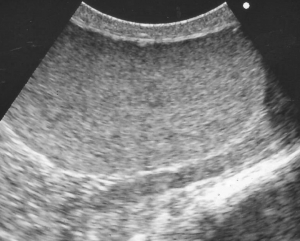

下の写真は精巣の超音波検査の画像です。正常な精巣は均一な画像(左)がみられますが、精巣炎・精巣上体炎の場合には異常に不均一なモザイク像が観察されます。